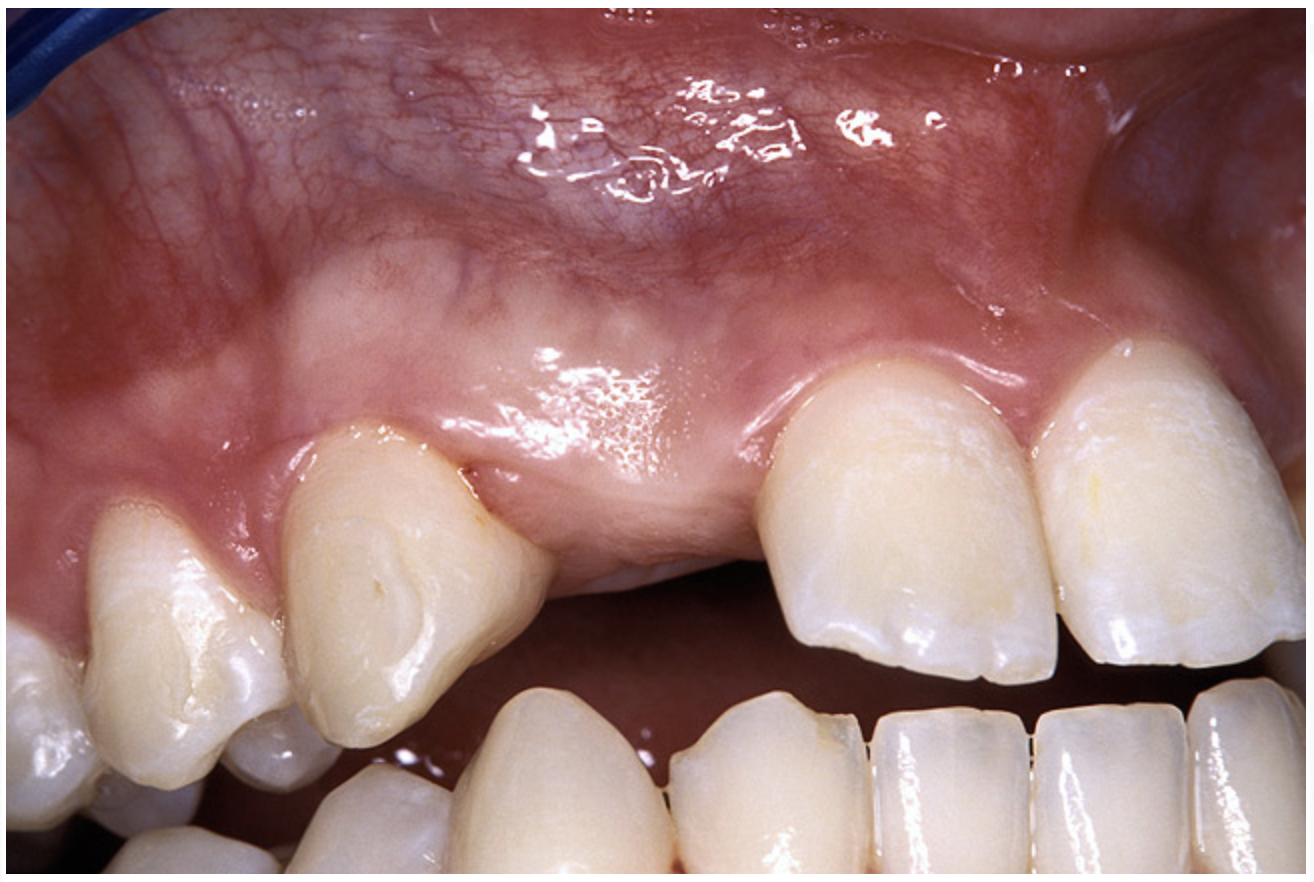

Periapical radiographs were taken to help determine the mesial-distal inclinations of the adjacent tooth roots (Figure 1). The radiographs revealed a serious issue, convergent roots for the right canine and right central, which eliminated that area as a potential implant-receptor site. The space between the left central and canine teeth was minimal, although the roots were relatively parallel. Clinical examination (manual palpation of the root eminences superiorly to the vestibule on the right side) confirmed the root convergence (Figure 2A). The flat, wide zone of the keratinized tissue and lack of interdental papilla was evident for the missing right lateral incisor. There was a marked difference in clinical appearance for the left lateral, which could impact the eventual plan of treatment (Figure 2B). Other significant clinical findings included bilateral facial bone concavities, which existed as a result of the congenitally missing tooth roots. As a diagnostic cue to the underlying bone topography, it is important to follow the demarcation between attached and unattached gingival tissue, and note the crestal width of the available keratinized tissue (Figure 2C).

Figure 2a  Pretreatment buccal views showed (A) root convergence, (B) a difference in clinical appearance of the left lateral, and (C) significant crestal width of keratinized tissue.

Figure 2b  Pretreatment buccal views showed (A) root convergence, (B) a difference in clinical appearance of the left lateral, and (C) significant crestal width of keratinized tissue.

Figure 2c  Pretreatment buccal views showed (A) root convergence, (B) a difference in clinical appearance of the left lateral, and (C) significant crestal width of keratinized tissue.